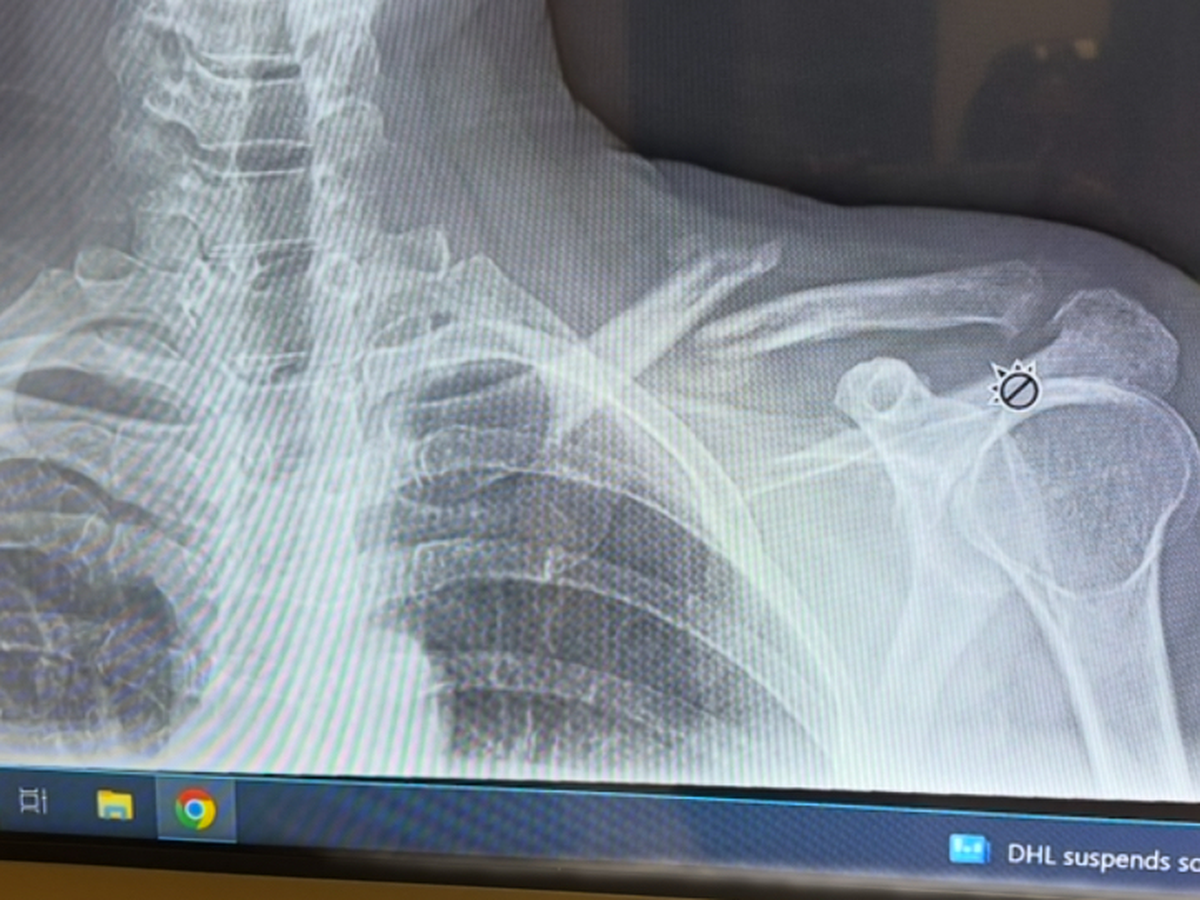

Hey friends and family, my name is April. I had a bad fall and broke my collarbone and kneecap. To try to avoid surgery, I'll be starting PT ASAP. I just started working again prior to the injury. I am asking for a little help to take some pressure off my sweetheart who has to carry me once again financially. Bills are piling up like crazy. Thank you kindly ❤️ I’ll be posting the pictures of the X-rays of my knee and shoulder very soon. My deductible is crushing us so I’ve opted to do PT at home for my knee. I’ll only have to go in for my shoulder. Thank you for your help, love and support!

thank you so much for your donations! I was able to get caught up with my health insurance and put some money towards the cc that I have maxed out using it for my doctor visits. I greatly appreciate your help. Please share my fundraiser with your friends and family. Any little amount helps greatly. I am so bummed to be out of work again. Staying positive and plugging along. Doctor said 6 weeks for my kneecap to heal. Shoulder Dr wants to see how I’m healing before we have to do surgery which would entail re breaking it, bone grafting along with a plate. After that heals , he would go back in to remove the plate. Praying I don’t have to go that route.

I saw the shoulder doctor today. Shoulder is slowly healing but I’m devastated as he said it will alway be messed up and slump down and forward. Also because of this and my knee , I feel again and have done something really back to my back. Having multiple severe spasms. I am going to see a spine specialist asap. Being in the car is super painful. Walking , but mostly sitting . Bummed. Thank you all for your support and kindness.